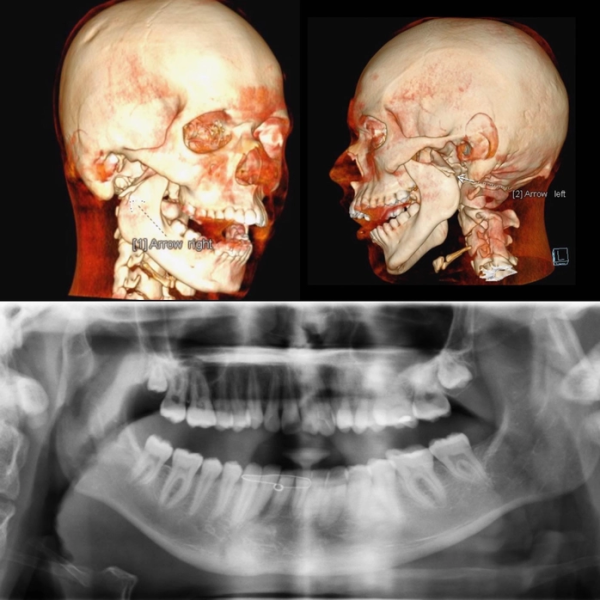

Bên cạnh đó, ứng dụng công nghệ hỗ trợ như chụp CT 3D, mô phỏng kỹ thuật số cũng có thể làm tăng tổng chi phí điều trị.